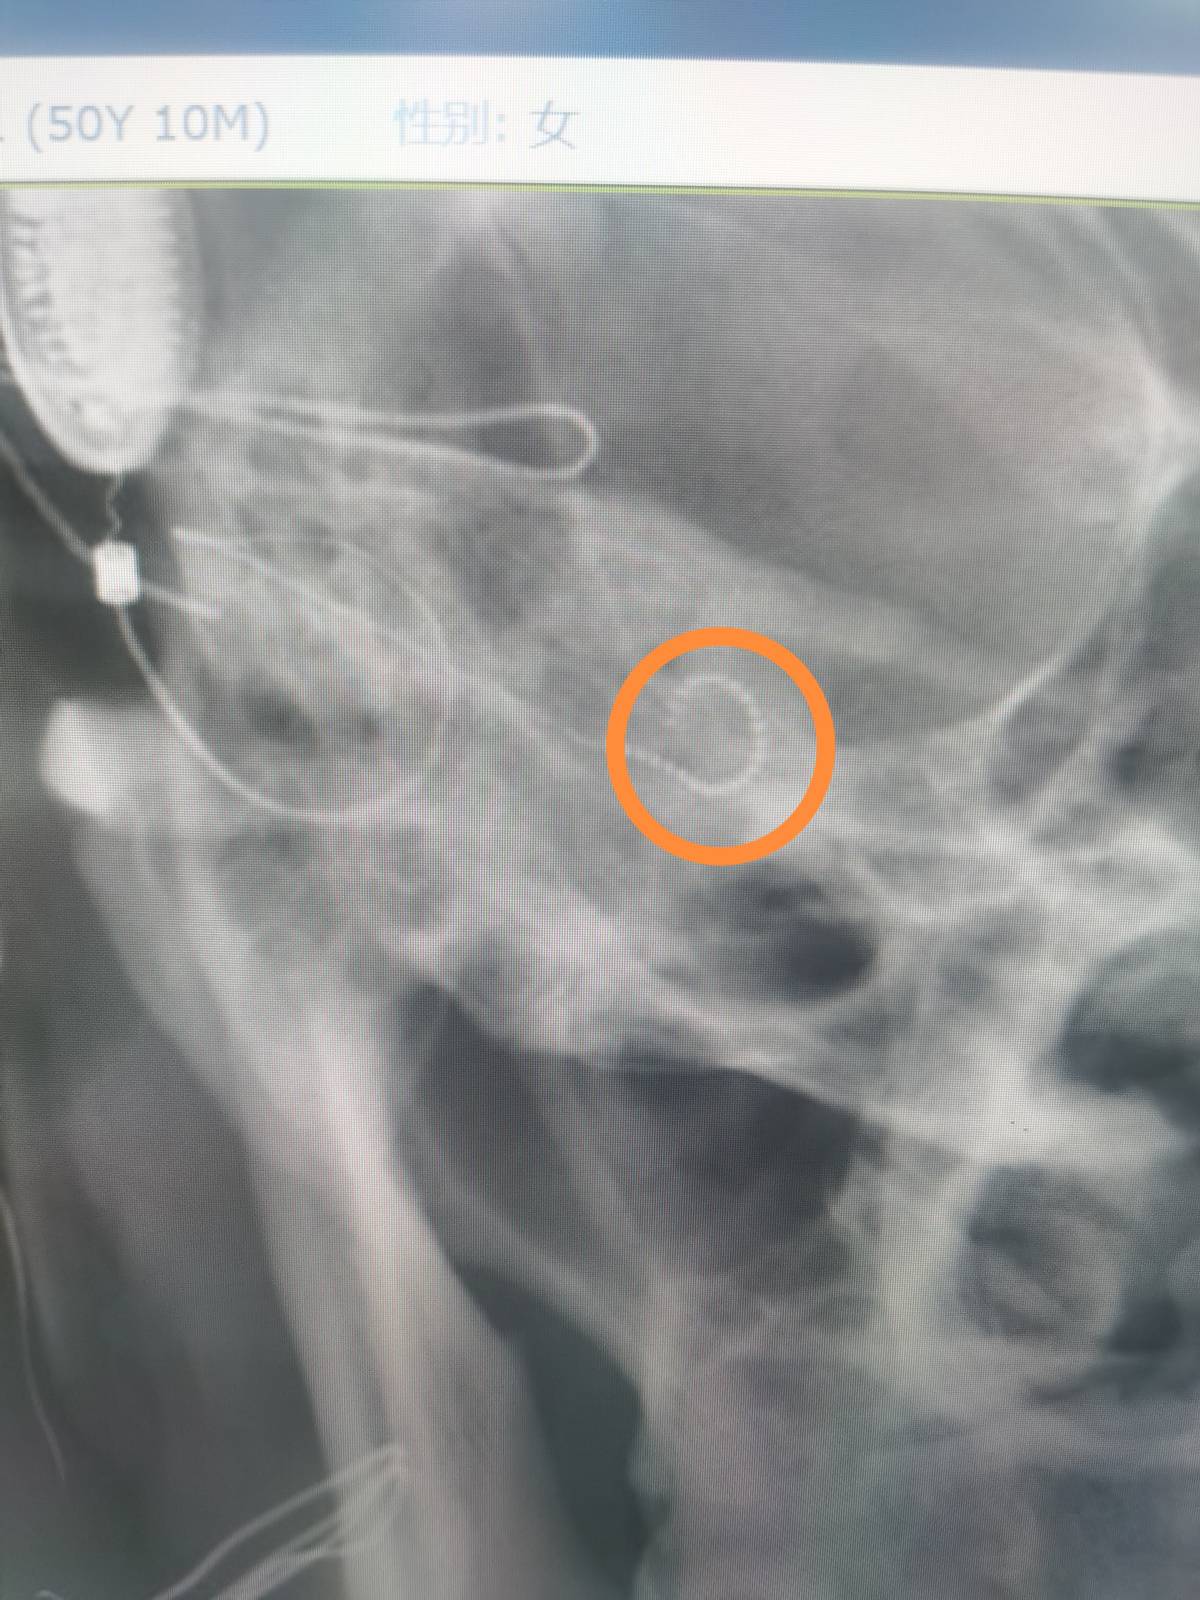

近日,南华大学附属第一医院耳鼻咽喉科同一天给两例患有双侧极重度感音神经性耳聋而佩戴助听器无效的患者开展人工耳蜗植入术,这也是衡阳市自主开展的第一例和第二例人工耳蜗植入术。此手术在科室主任江青山教授的指导下,由科室副主任陈祖尧博士主刀完成,手术顺利,术中电极阻抗测量以及神经反应测试皆为正常,术后第二天的头颅X片提示植入电极在耳蜗内布阵良好,表明手术取得了成功。患者需要做的就是等待一个月以后的开机调试和言语康复。

术后颅骨X片显示耳蜗植入电极位置正常